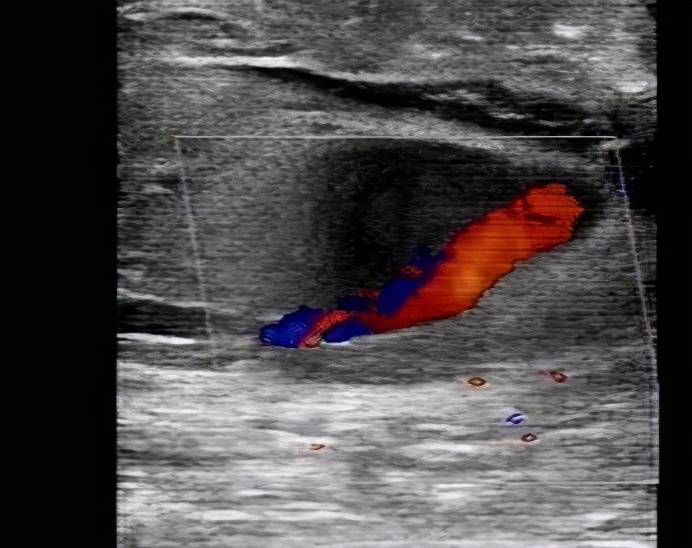

文章图片

【夹层|真性动脉瘤、假性动脉瘤、夹层动脉瘤特点及表现】股动脉穿刺介入治疗后 , 股浅动脉管壁连续性中断 , 可见撕裂口有血流喷射 。 该病灶内探及动脉样频谱 , 超声提示:外伤后假性动脉瘤形成 。